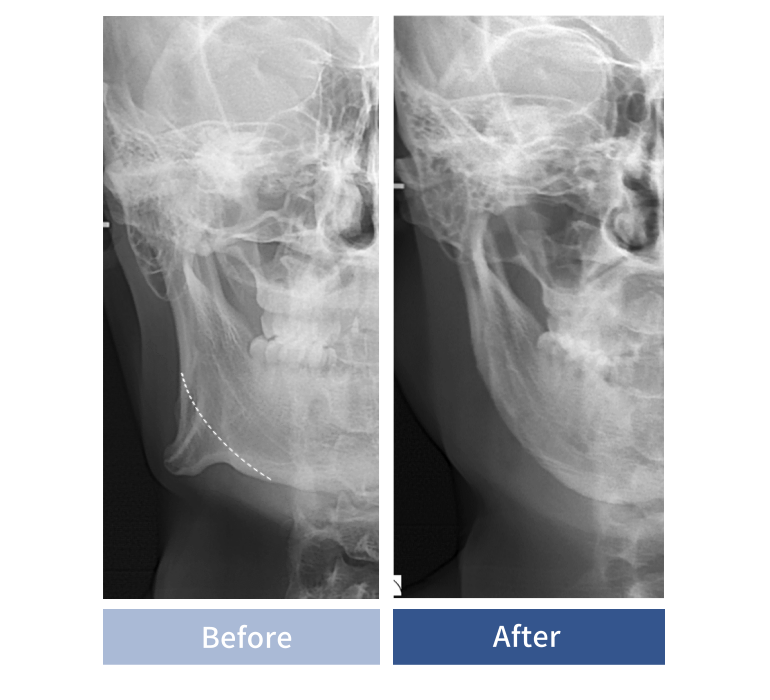

파라디아 사각턱축소술 실제 수술 환자 CT

안전하고 정교한 수술로 수술후 CT 검사 경과 체크

수술후 수술 부위 고정 및 뼈 축소 확인을 위한 CT검사와 경과 체크를 진행.